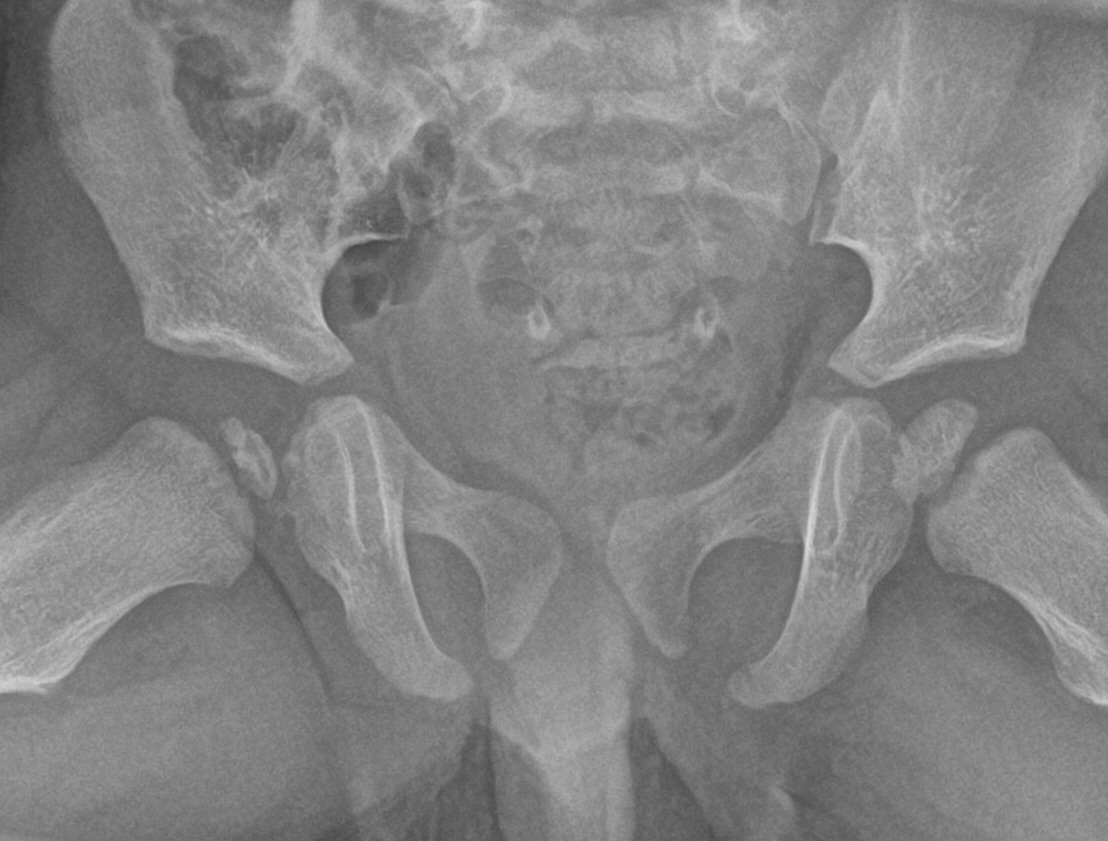

Perthes sjukdom i höger höft, Lauensteinprojektion

- Slätröntgen av bäcken och höfter.